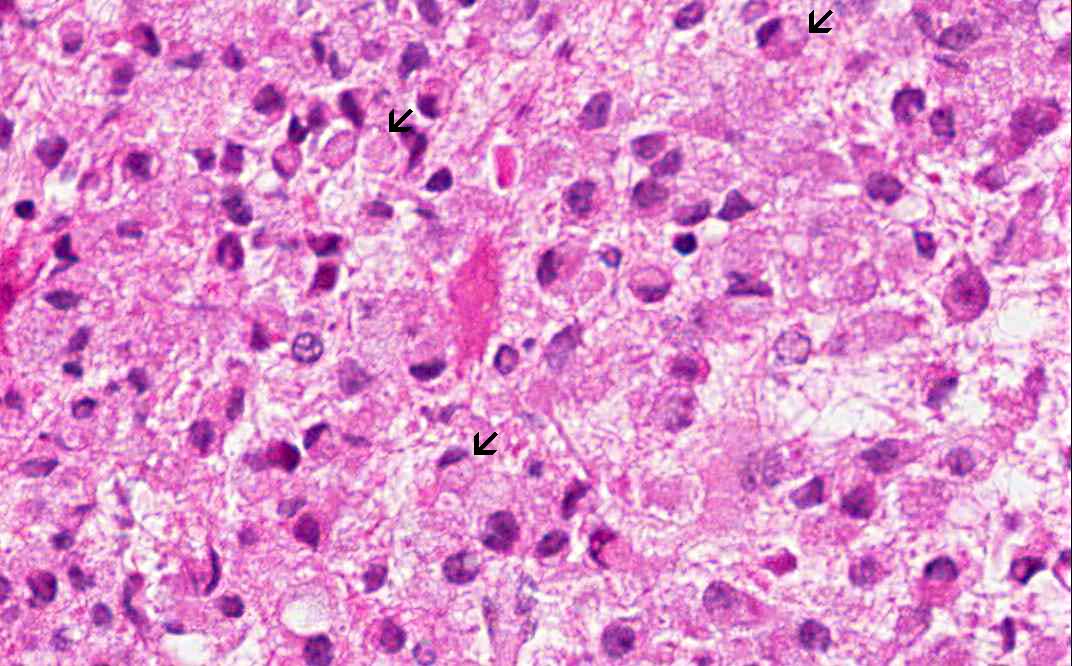

Area 1: This image is taken at the interface of the area extensively infiltrated by macrophages (M) and area far less significantly infiltrated by foamy macrophages and many reactive astrocytes (white arrows) are present in this area. On high magnification, note that the foamy histiocytes have a moderate amount of cytoplasm with a bubbly or foamy appearance. Hence they are called foamy macrophages.